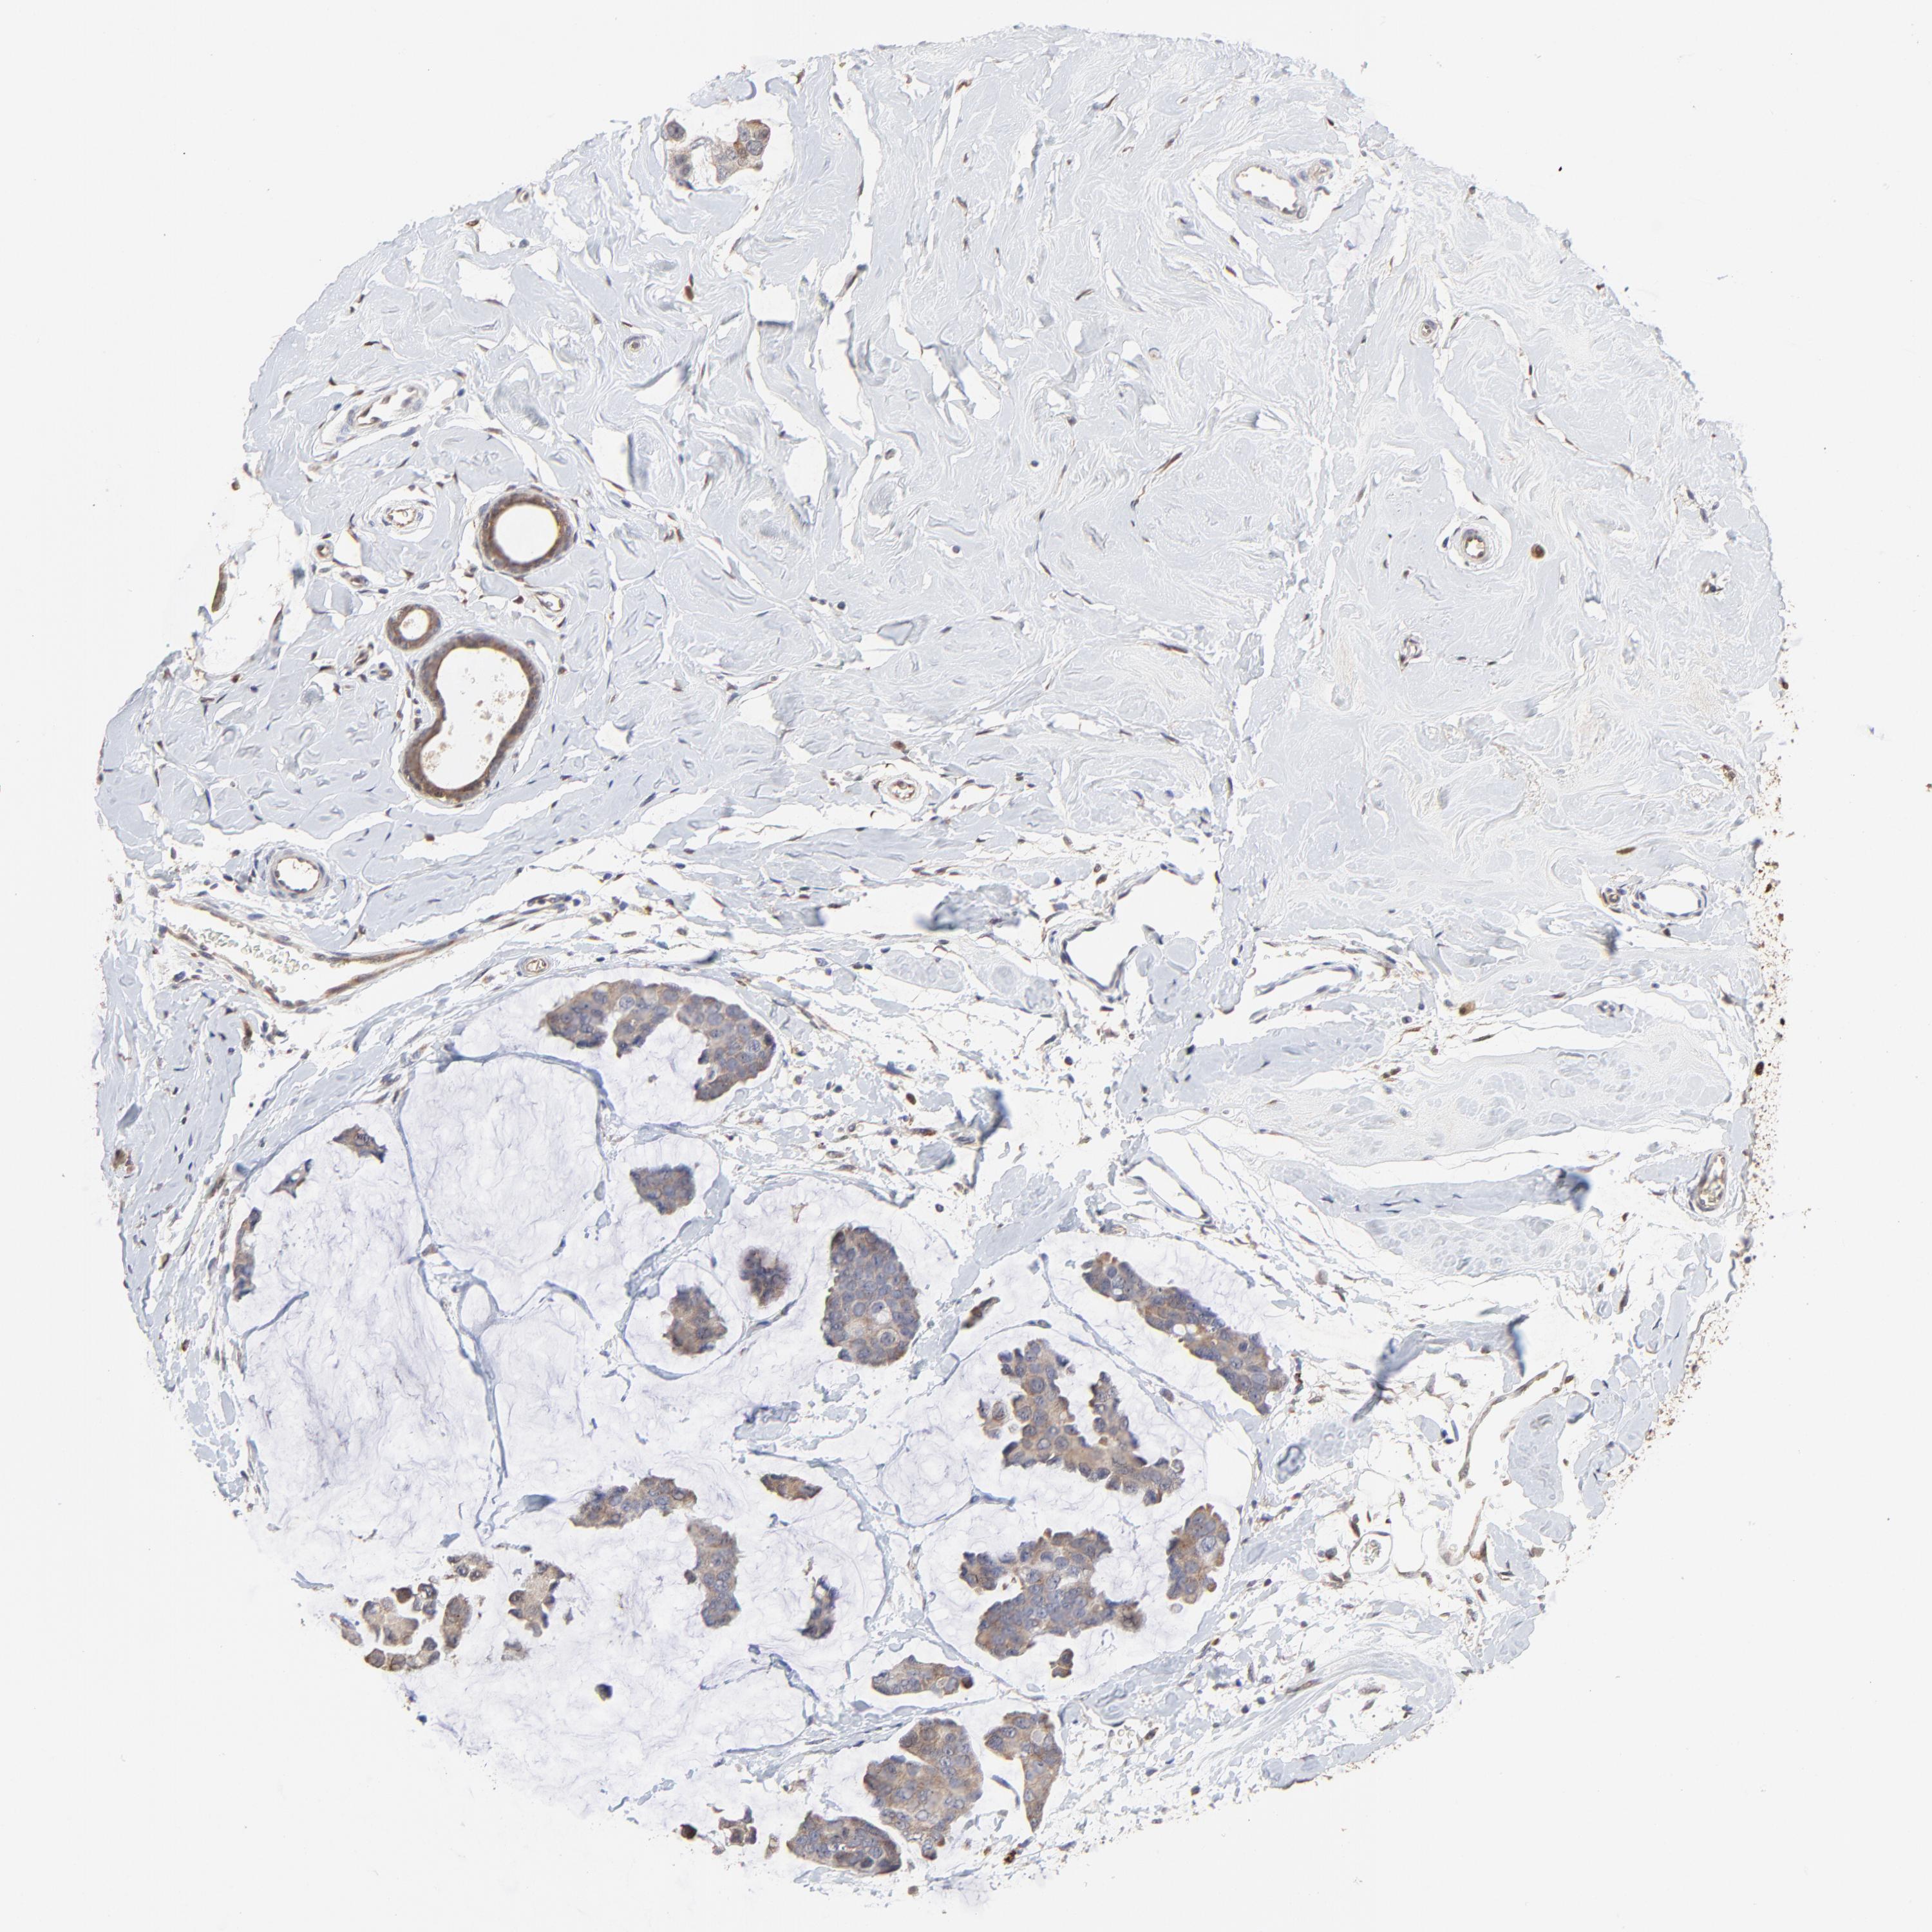

CANCER BREAST CANCER Show tissue menu

BRCA TCGA BRCA VALIDATION PROTEIN EXPRESSION

ANTIBODIES

AND

VALIDATION